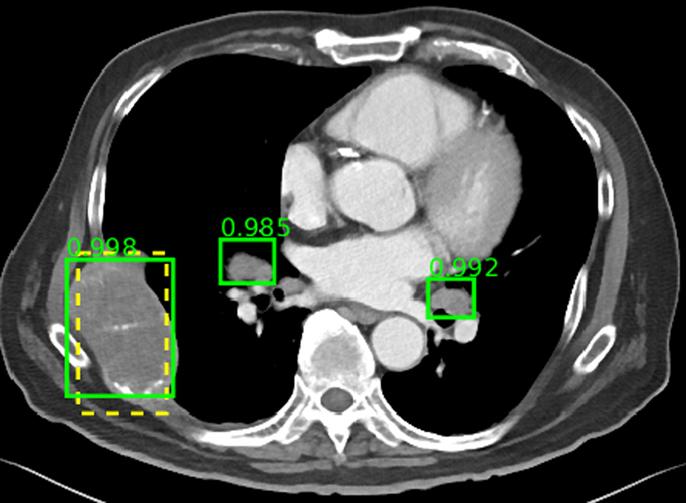

image: The ground-truth and two enlarged lymph nodes are correctly detected, even though the lymph nodes are not annotated in the dataset.

The database includes multiple lesion types, including kidney lesions, bone lesions, lung nodules, and enlarged lymph nodes. The lack of a multi-category lesion dataset to date has been a major roadblock to development of more universal CADe frameworks capable of detecting multiple lesion types. A multi-category lesion dataset could even enable development of CADx systems that automate radiological diagnosis.

In addition to building the database, the team also developed a universal lesion detector based on the database. The researchers note that lesion detection is a time-consuming task for radiologists, but a key part of diagnosis. This detector may be able to serve as an initial screening tool for radiologists or other specialist CADe systems in the future.